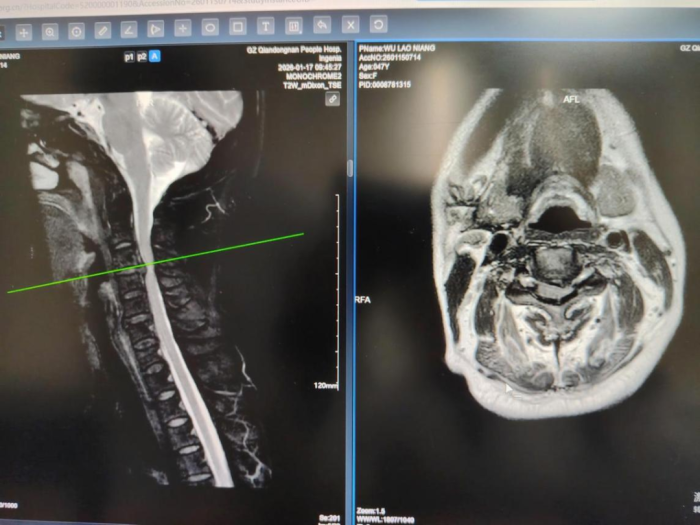

47岁的吴阿姨多年来反复颈肩部痛折磨,近1个月病情加重,出现右侧肢体麻木,左侧肢体无力、行走不稳的情况。从最初的轻微症状到后来彻夜难眠的剧烈麻痛,吴阿姨尝试过多种治疗方式,药物治疗、理疗、针灸......效果却微乎其微,甚至一天比一天严重,日常生活逐渐受到限制。韩凡主治医师接诊,经检查后发现吴阿姨的症状是因为C3/4巨大颈椎间盘突出压迫神经引起的。经科室讨论后,在帮扶专家余铃教授与脊柱外科主任杨标博士的指导下,由张庭维、韩凡主治医生实施颈椎内镜下椎间盘髓核摘除手术(颈椎UBE技术),术中患者神经根实现完全减压,术后患者症状明显改善,术后第2天便恢复下床行走。术后5天即办理出院。

术前

术中

术后